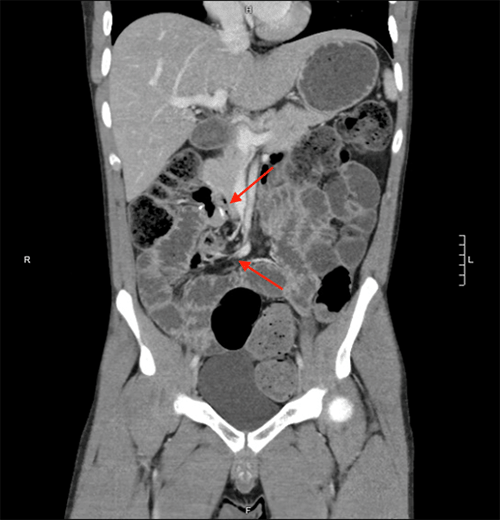

The patient is a 25-year-old man with a history of obstructing ileocolonic Crohn's disease requiring laparoscopic ileocolic resection. One year after the resection, he had superior mesenteric artery syndrome treated with a laparoscopic duodenojejunostomy. His Crohn's was managed with long-term prednisone and ustekinumab after previously failing adalimumab, certolizumab, infliximab, and vedolizumab. Two months before this hospitalization, a CT scan demonstrated normal orientation of both duodenojejunal and ileocolic anastomoses (Figure 1).

Figure 1. CT Scan Demonstrating Normal Orientation of Stapled Ileocolic Anastomosis (Lower Arrow) and Stapled Duodenojejunstomy (Upper Arrow). Published with Permission